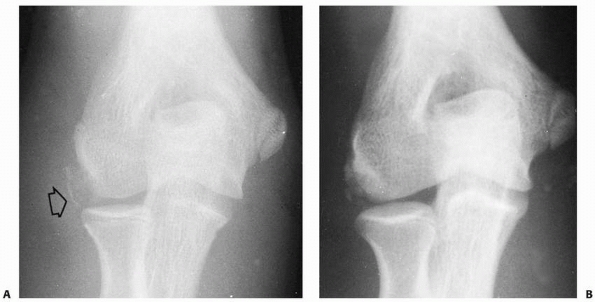

![]() |

FIGURE 15-2 Physeal fractures of the lateral condyle. A. Physeal injury (Milch type II) through the nonossified trochlea. B.

Physeal injury (Milch type I) through the ossific nucleus of the lateral condyle. (Adapted and reprinted with permission from Milch HE. Fractures and fracture-dislocations of the humeral condyles. J Trauma 1964;4:592-607.) |